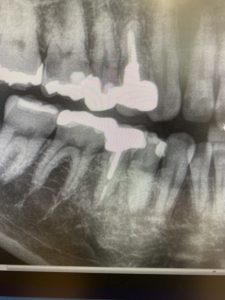

上の写真は一般的なパノラマで撮影してものですが、いまいち右下の状況が判断しずらくなっています。

一方、下の三枚はCT画像なのですが、右下の小臼歯が破折しているのがわかります。